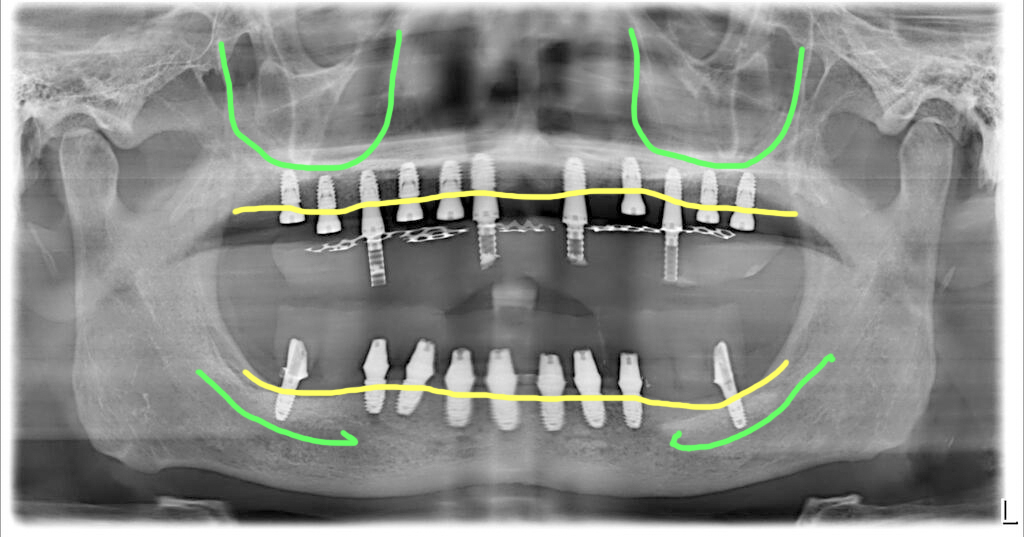

상악에는 11개, 하악에는 9개 식립 수술당일 임시치아

상악에는 치조골이 골고루 남아있기는 했으나 길이가 충분하지는 않았습니다. 하지만 무리하게 긴 임플란트를 선택하지 않고 충분한 개수로 식립하는 방식으로 치료를 했습니다.

하악은 뼈가 너무 딱딱해서 짧은 길이로 식립을 했습니다. 골질이 너무 단단한 경우 무리하게 드릴링을 할 경우 뼈가 과열될 수 있어 문제가 됩니다. 그래서 골질이 너무 단단한 경우에는 무리하게 긴 임플란트를 식립하려고 하지 않습니다.

4회 내원 치료기간 5개월 전체임플란트 치료완료

수술 후 5개월에 최종보철을 준비해서 세팅했습니다. 아래쪽 어금니 부분에 지르코니아 브릿지 부분이 파절이 되어 해당 부분은 티타늄으로 한 번 교체했습니다.

이렇게 지르코니아로 브릿지를 할 경우 교합력에 의해 파절이 생기는 경우가 있습니다. 이 분의 경우 허공에 떠 있는 인공치 부분에 임플란트 식립이 어려워 재료를 금속으로 교체했지만 만약 뼈가 허락된다면 인공치 부분에 추가 임플란트를 심어서 해결하는 경우도 있습니다.

이 분은 치료 받으신 지 5년이 되었고, 현재 정기체크 잘 받고 계십니다.